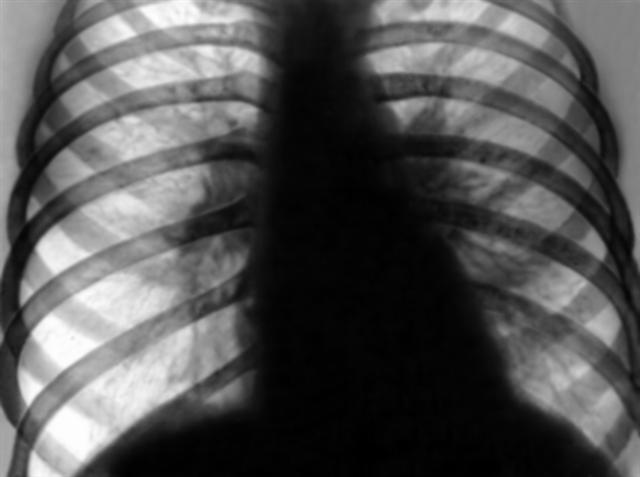

Рис. 11а). Рентгенограмма грудной клетки больного с декомпенсированным митральным стенозом: до операции комиссуротомии (резко выражен застой в легких).